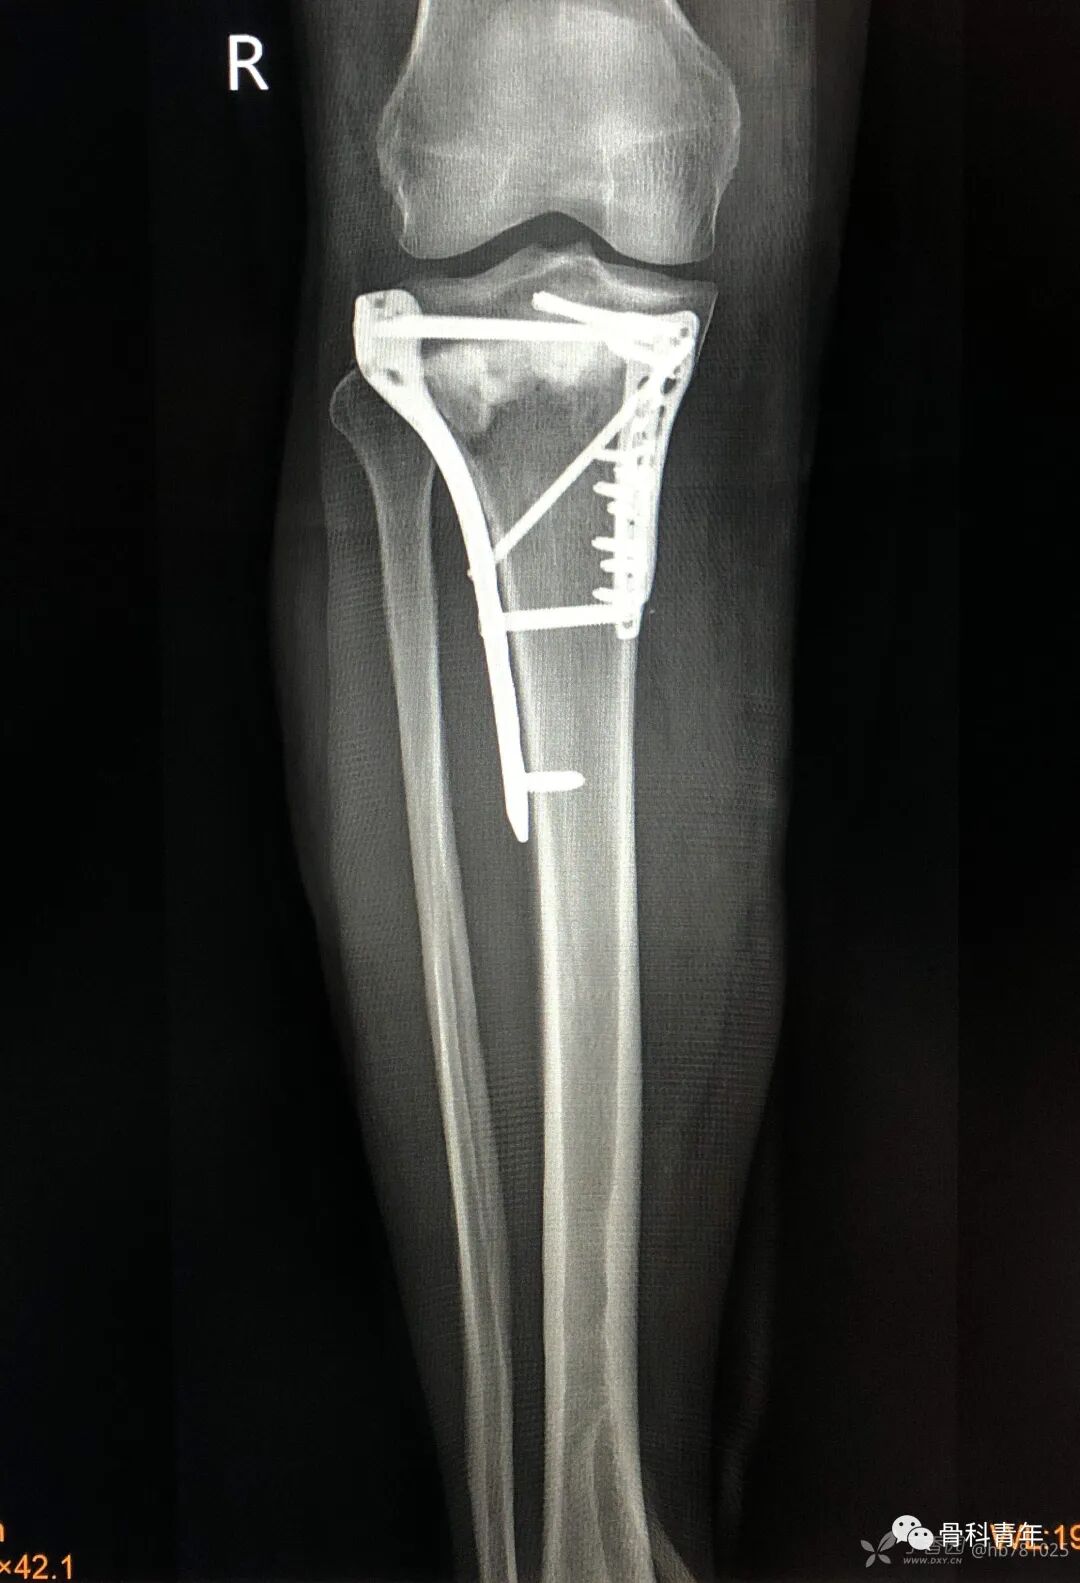

6.胫骨平台骨折(过伸伤)

8.胫骨结节撕脱性骨折